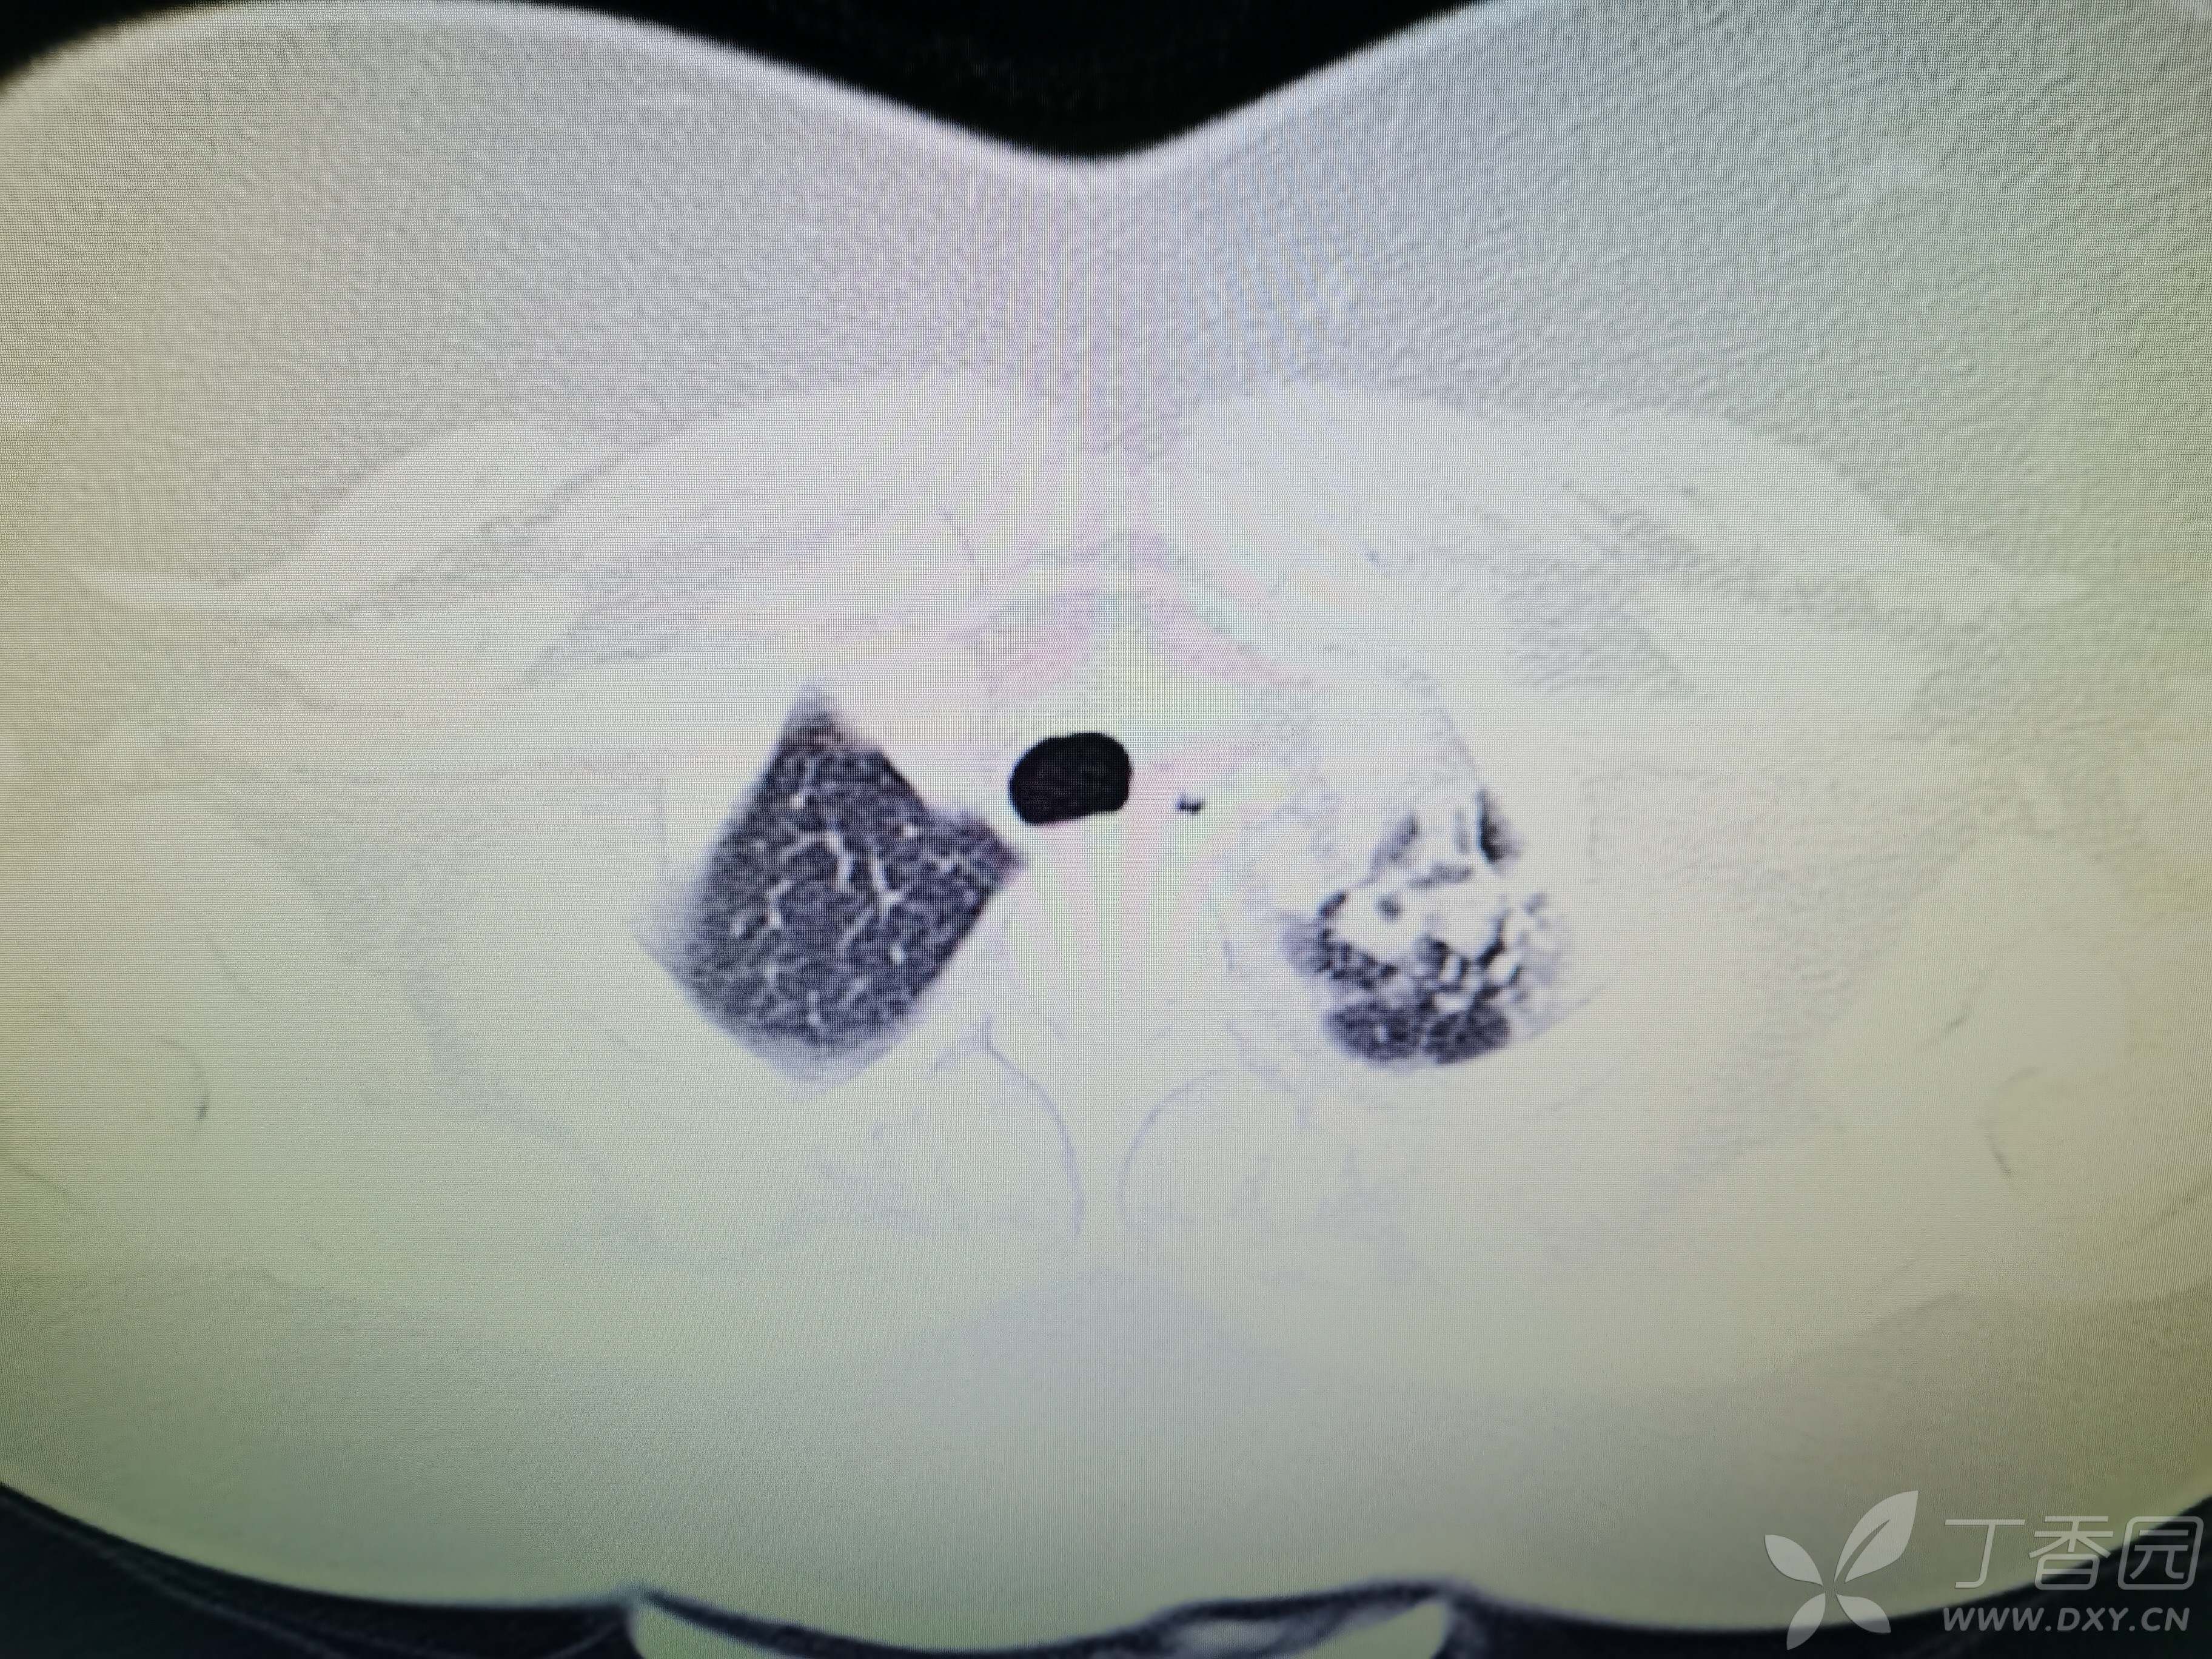

基本信息:女,三十几岁,印度人。。

胸部CT:

如题:猜肺部病灶病理。。